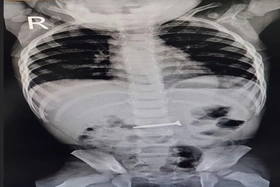

baophutho.vn Trung tâm Y tế huyện Thanh Thủy vừa cấp cứu thành công một trường hợp bé trai 2 tuổi trú tại xã Đồng Trung, huyện Thanh Thủy, bị dị vật là...